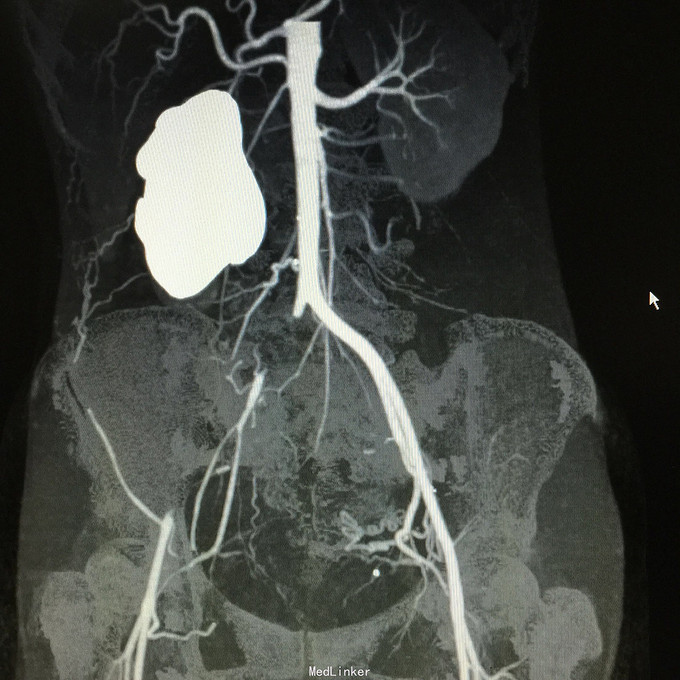

查体无特殊。 辅助检查:中下腹CT平扫+增强+CTU+CTA示:1.右输尿管中上段病变,考虑恶性病变,周围多发淋巴结转移,髂总动脉及髂外动脉起始部、髂内动脉中上段受侵闭塞,右侧腰大肌可疑受侵;建议输尿管镜检查;右肾重度积水,右肾功能明显受损。2.CTA示:右肾动脉纤细,肝右动脉起源于肠系膜上动脉。3.子宫体密度不均匀,建议MRI检查。中下腹MRI平扫+增强+MRU检查结果类似。

患者术后2月出现反复臀部疼痛,左侧为主,疼痛跑迷宫为隐痛,于翻身及活动时加重,卧床休息可稍缓解,多于下午出现,伴有发热,最高达39℃,在当地医院予“氟康唑”及止痛治疗后稍有缓解,但仍反复发热。后疼痛加剧,并出现双下肢疼痛,以大腿外侧为主,无间歇性跛行,无小腿及双足麻木疼痛不适,行对症治疗后效果不佳,于2015-10-9再次返院,予消炎止痛、营养支持及营养神经等治疗。查CT及MRI均提示骶髂关节炎症及腹膜后巨大病变,右侧髂总动脉及髂内、外动脉上段、右侧腰大肌受累。2015-10-15 14:00患者出现右下肢剧烈疼痛、右下肢乏力和麻木,随后出现2次血便,每次量约100ml,暗红色,无腹胀、腹痛等不适,查血提示白细胞 28.17*10E9/L,中性粒绝对值 25.33*10E9/L,血红蛋白56g/L,予止血、输血、抗真菌、止痛等治疗。19:00再次出现右下肢剧烈疼痛伴右下腹痛,查体:BP 80-90/50-60mmHg,P 100-106次/分,R 23次/分,SpO2 100%。右下腹轻压痛,反跳痛阴性,右下肢蹲背伸及踝背伸肌力II-III级,立即行全腹CT检查,示右髂总动脉假性动脉瘤破裂,予加强输注浓缩红细胞及补液支持治疗。清介入科会诊,考虑脓肿和感染为介入血管腔内支架置入治疗的禁忌症,建议予血管外科行开放手术,予患者及家属沟通,并转外院血管外科进一步治疗。